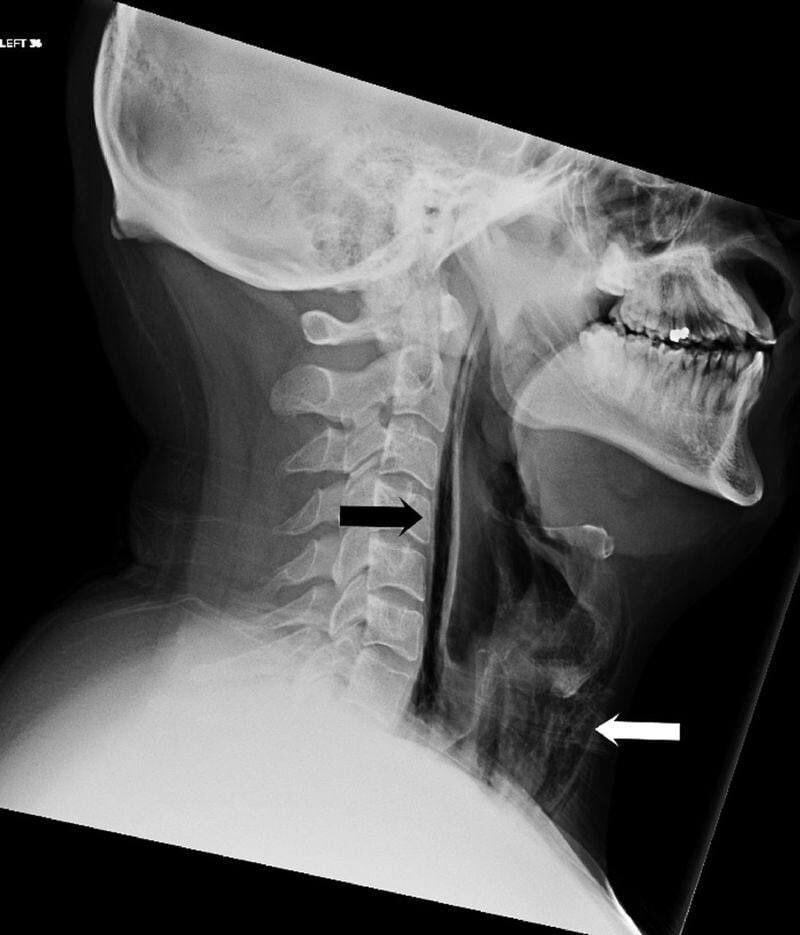

Мужчина поступил в Суоярвскую ЦРБ с жалобами на острую боль при глотании и на изменения в голосе после сильного чиха. Рентген показал, что у 34-летнего пациента произошел спонтанный разрыв пищевода. Об этом сообщили в паблике ГБУЗ «Суоярвская ЦРБ».

«Он попытался сдержать позыв чихнуть, зажав ноздри пальцами, но когда чихнул, то почувствовал толчки в шее и затем обнаружил, что шея опухла. Пациенту сделали рентгенограмму, на которой видно чрезмерное скопление воздуха в мягких тканях шеи перед трахеей. Поставлен диагноз: спонтанный разрыв пищевода. Такая практика зажимать рот и нос, чтобы не чихать, является опасной, и делать этого не следует. К возможным последствиям такого маневра относится эмфизема средостения (аномальное скопление воздуха в анатомическом пространстве в средних отделах грудной полости), перфорация барабанной перепонки и даже разрыв аневризмы головного мозга», — сообщили врачи.